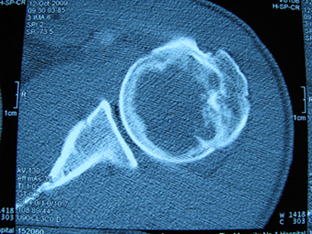

标题: X6404B:肱骨骨质破坏(CT片) [打印本页]

标题: X6404B:肱骨骨质破坏(CT片)

男,50岁,左肩部轻微疼痛,活动不便5个月就诊,近十天加重,无红肿热,间断理疗治疗无好转,既往5个月前左肩轻微拉伤史

骨巨?动脉瘤样骨囊肿?

内生软骨瘤。

内生软骨瘤。

内生软骨瘤?-----------

年纪大了,先要排除转移瘤。

髓腔内软组织肿块并斑片状钙化,考虑高分化软骨肉瘤可能性大。

考虑骨巨或动脉瘤样骨囊肿。

内生软骨瘤可能性大,期待结果。

孤立性骨囊肿。

内生软骨瘤可能性大

其内可见钙化,考虑软骨源性肿瘤,内生软骨瘤可能

但由于年龄较大,恶性软骨肉瘤待排

肱骨头内巨大软组织肿块并斑片状钙化,内生软骨瘤?骨巨细胞瘤?软骨粘液样纤维瘤?期待结果!

髓腔内软组织肿块并斑片状钙化,考虑高分化软骨肉瘤可能性大。

内生软骨瘤可能性大

肱骨头内巨大软组织肿块并斑片状钙化,内生软骨瘤?骨巨细胞瘤?软骨粘液样纤维瘤?期待结果

考虑内生软骨瘤?骨巨细胞瘤?

内生软骨瘤?骨巨细胞瘤?

先要排除转移瘤。